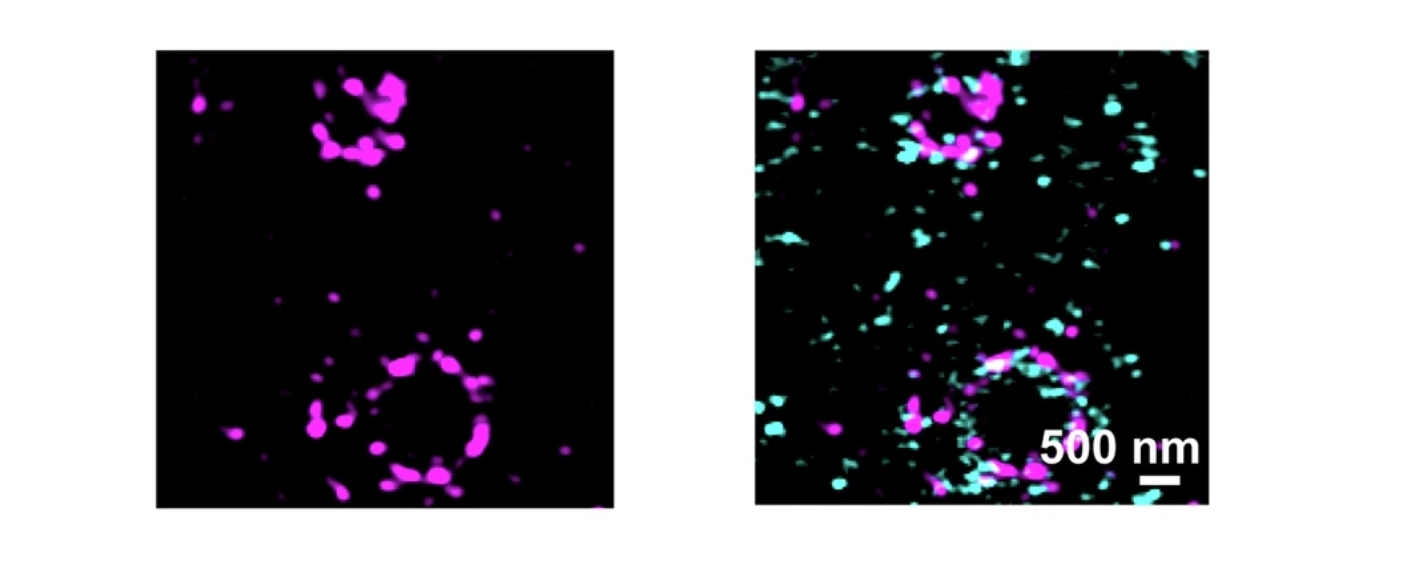

In dieser Studie untersuchten die Arbeitsgruppen von Prof. Dr. Carmen Villmann (Institut für klinische Neurobiologie), Prof. Dr. Kathrin Doppler (Neurologische Klinik) und Dr. Hans Maric (Rudolf-Virchow-Zentrum) über Bindung an Deletionsmutanten und Peptid-Microarrays, ob verschiedene Epitope mit bestimmten klinischen Phänotypen assoziiert sind. Die Forschenden fanden heraus, dass dies tatsächlich der Fall ist. Die Studie zeigt, dass die Erkrankung heterogener ist als bislang angenommen. Das Vorliegen verschiedener Epitope innerhalb der Erkrankung deutet auf verschiedene Auslöser der Autoimmunreaktion und verschiedene Effekte der Autoantikörper im Gewebe hin. Die Bestimmung der Epitope könnte somit ein Prognosefaktor für die Erkrankung des einzelnen Patienten sein.